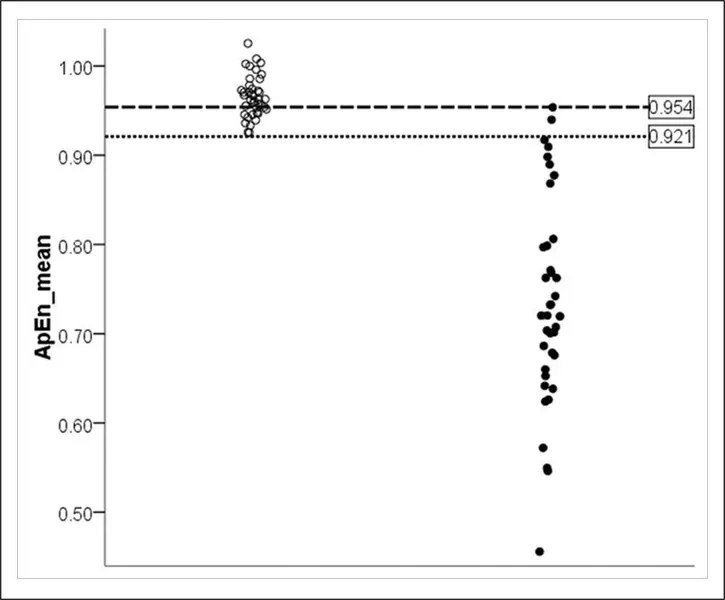

Isolamento Funzionale all’Interno della Corteccia Cerebrale nello Stato Vegetativo: un Metodo non Lineare per Prevedere gli Esiti Clinici

Lo studio utilizza l’analisi non lineare dell’EEG per valutare la complessità cerebrale nei pazienti in stato vegetativo, mostrando come la riduzione dell’entropia sia associata a un minore recupero della coscienza e a esiti clinici peggiori.